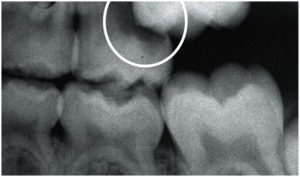

Below is an example of a permanent molar not erupting properly because it is stuck underneath the adjacent baby tooth. Drs. Mary Paula and/or Henry will be able to properly diagnose and recommend an appropriate remedy for this problem.